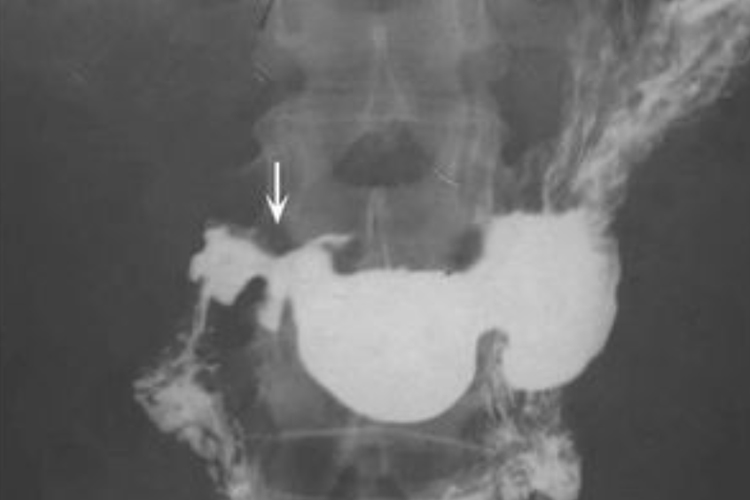

胃肠道肿瘤:局部充盈缺损,形状不规则,管腔狭窄,管壁狭窄,龛影,边缘不整,位于管腔轮廓内,黏膜皱襞破坏,中断,消失。